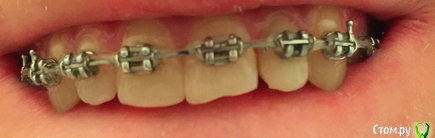

Zubik_Zubik Опубликовано 18 февраля, 2019 Поделиться Опубликовано 18 февраля, 2019 (изменено) Добрый день!22 депульпирован более 10 лет назад. пломба, затем реставрация, брекеты, сейчас повторная реставрация чтобы приклеить ретейнер.Скололся из за нависающего края на медиальной стороне.1. Что разумнее сделать?- предлагают устранить скол пломбой- снять так, ортопедия 4 зуба например. 2. можно ли будет поставить коронку если пломба у десны при условии что хочу все красиво?)Спасибо! Изменено 18 февраля, 2019 пользователем Zubik_Zubik Ссылка на комментарий

Zubik_Zubik Опубликовано 1 марта, 2019 Автор Поделиться Опубликовано 1 марта, 2019 (изменено) Как смог нарезал в кт. 1.Ортопед сказал что с небной подрезать нужно чутка.2.Насколько разумен такой вариант пока установлены брекеты. Спелить пломбу переклеить брекет с целью экструзии зуба, потом снова пломба и ретейнер. После небольшого отдыха нормальная коронка +3 винира 21, 11, 12. Спасибо Изменено 1 марта, 2019 пользователем Zubik_Zubik Ссылка на комментарий